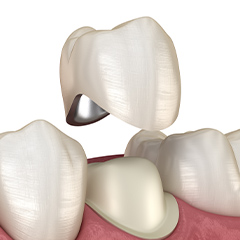

인레이보다 넓은 범위의 충치일 때 치아 전체를 단단한 크라운으로 씌우며

내 치아 같은 자연스러움이 장점입니다.